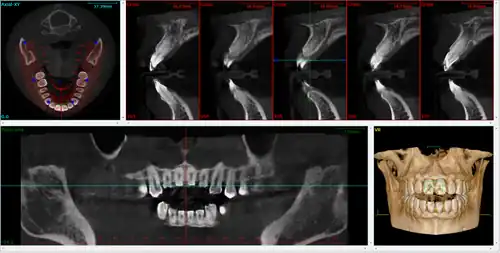

Cone beam computed tomography (or CBCT, also referred to as C-arm CT, cone beam volume CT, flat panel CT or Digital Volume Tomography (DVT)) is a medical imaging technique consisting of X-ray computed tomography where the X-rays are divergent, forming a cone.[1]

CBCT has become increasingly important in treatment planning and diagnosis in implant dentistry, ENT, orthopedics, and interventional radiology (IR), among other things. Perhaps because of the increased access to such technology, CBCT scanners are now finding many uses in dentistry, such as in the fields of oral surgery, endodontics and orthodontics. Integrated CBCT is also an important tool for patient positioning and verification in image-guided radiation therapy (IGRT).

During dental/orthodontic imaging, the CBCT scanner rotates around the patient's head, obtaining up to nearly 600 distinct images. For interventional radiology, the patient is positioned offset to the table so that the region of interest is centered in the field of view for the cone beam. A single 200 degree rotation over the region of interest acquires a volumetric data set. The scanning software collects the data and reconstructs it, producing what is termed a digital volume composed of three-dimensional voxels of anatomical data that can then be manipulated and visualized with specialized software.[2][3] CBCT shares many similarities with traditional (fan beam) CT however there are important differences, particularly for reconstruction. CBCT has been described as the gold standard for imaging the oral and maxillofacial area.

A dental cone beam scan offers useful information when it comes to the assessment and planning of surgical implants. The American Academy of Oral and Maxillofacial Radiology (AAOMR) suggests cone-beam CT as the preferred method for presurgical assessment of dental implant sites.[20]

As a 3D rendition, CBCT offers an undistorted view of the dentition that can be used to accurately visualize both erupted and non-erupted teeth, tooth root orientation and anomalous structures, that conventional 2D radiography cannot.[21]